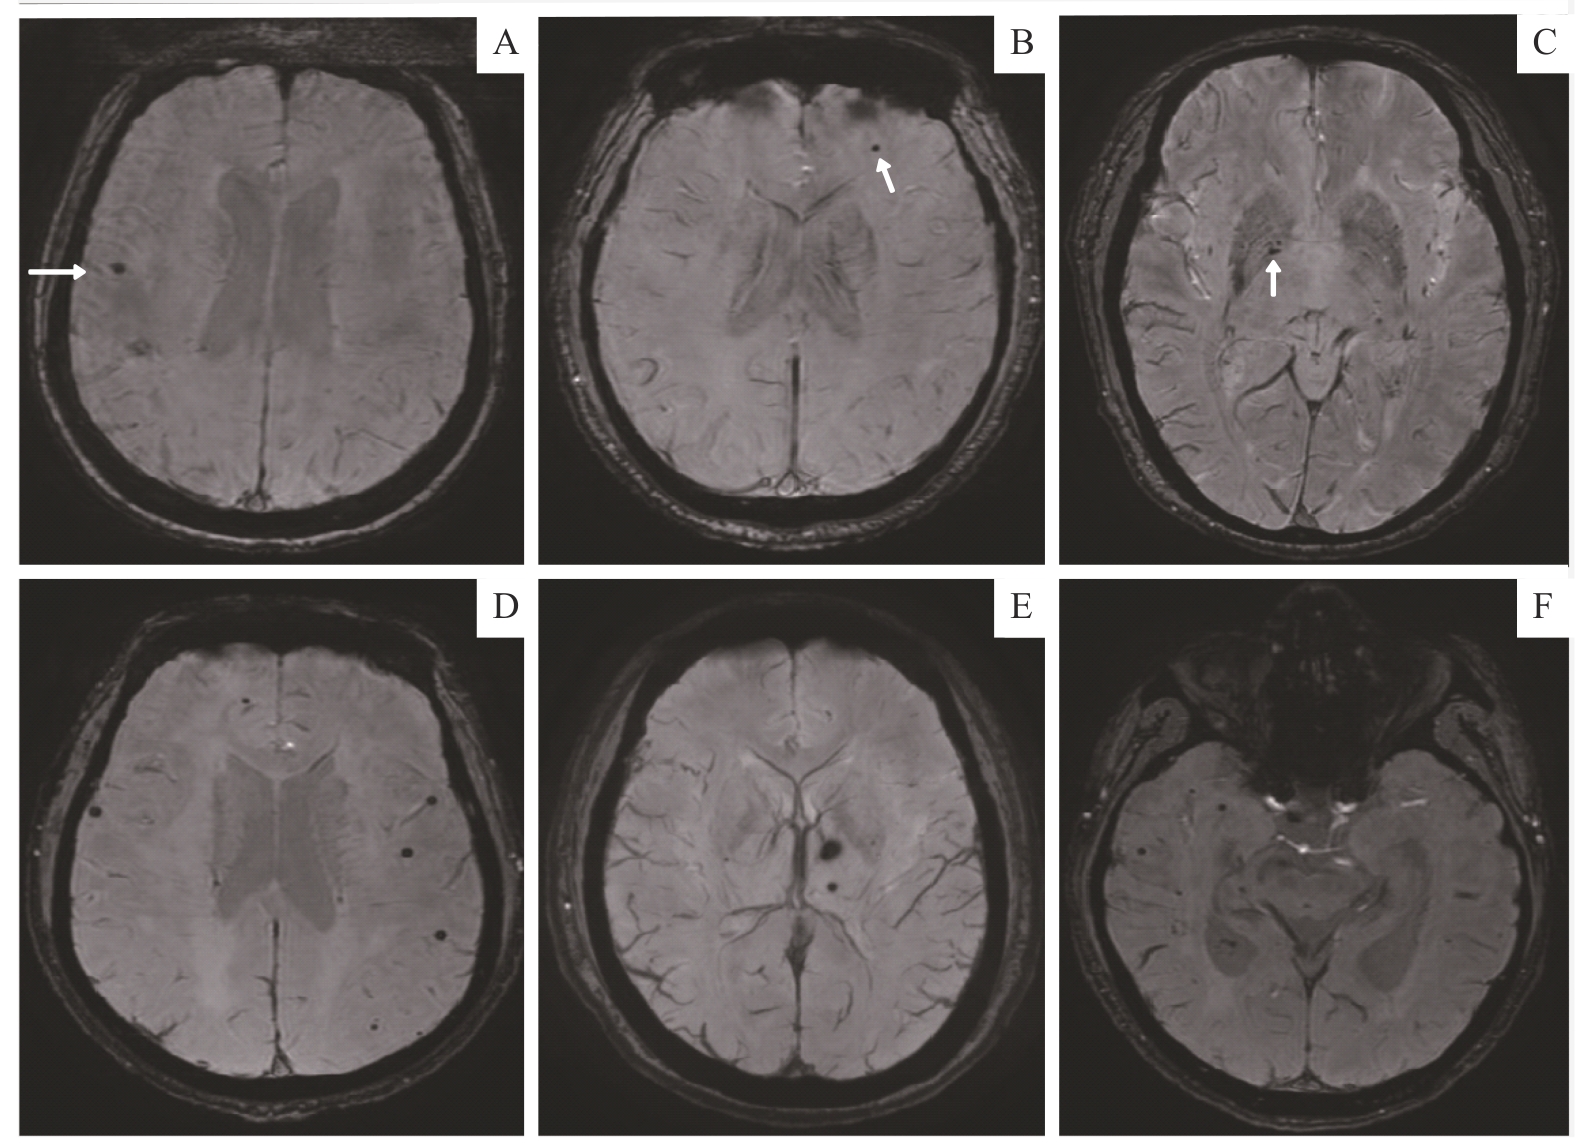

目的·采用磁敏感加权成像(susceptibility-weighted imaging,SWI)评估终末期肾病(end-stage renal disease,ESRD)患者大脑微出血灶的数量、分布,探究SWI所呈现的影像特征与患者认知功能损伤关系。方法·纳入2023年1月—2024年3月在上海交通大学医学院附属第六人民医院行透析治疗>1年的ESRD住院患者。予患者行常规磁共振成像序列检查及SWI检查,记录患者大脑微出血灶的数量,以及其在不同脑区的分布情况。同时,采用蒙特利尔认知评估量表(Montreal Cognitive Assessment,MoCA)对患者的认知功能进行评估。将MoCA≥26分者归为ESRD无认知障碍组,<26分者为ESRD合并认知障碍组。评估患者大脑微出血灶的有无及数量与是否存在认知障碍的关系,探究合并认知障碍的ESRD患者大脑微出血灶在其大脑各区域的分布情况,以及特定脑区大脑微出血灶数量与患者认知损伤程度的相关性。结果·共38例患者纳入研究,其中,ESRD合并认知障碍组16例,ESRD无认知障碍组22例。大脑微出血灶在ESRD合并认知障碍组出现概率更高(14例,占87.50%),而在无认知障碍组出现概率较低(12例,占54.55%),差异有统计学意义(P=0.033)。ESRD合并认知障碍组大脑微出血灶数量更多(106个),且主要分布于双侧皮层及皮层下区(59.43%)和基底节区(19.81%);无认知障碍组大脑微出血灶数量较少(47个),主要分布于双侧基底节(46.80%)、皮层及皮层下区(40.43%),差异均具有统计学意义(均P<0.05)。合并认知障碍者,皮层及皮层下区微出血灶数量与认知损伤程度呈显著负相关(r=-0.718,P=0.030)。结论·由SWI检出的ESRD患者大脑微出血灶数量及分布与其认知障碍的有无及严重程度存在相关性。通过SWI可以发现ESRD患者大脑微出血灶的形成及分布,进而评估患者认知障碍程度。

Objective ·To assess the number and distribution of cerebral microbleeds (CMBs) in patients with end-stage renal disease (ESRD) using susceptibility-weighted imaging (SWI), and to explore the relationship between SWI-detected imaging features and cognitive impairment. Methods ·Hospitalized ESRD patients who had received dialysis treatment for more than one year at Shanghai Sixth People's Hospital, Shanghai Jiao Tong University School of Medicine, between January 2023 and March 2024 were included. All patients underwent conventional MRI sequences and SWI scanning. The number and regional distribution of CMBs were recorded. Cognitive function was assessed using the Montreal Cognitive Assessment (MoCA). Patients with MoCA scores ≥26 were classified into the ESRD without cognitive impairment group, and those with scores <26 were placed in the ESRD with cognitive impairment group. The presence and number of CMBs were analyzed in relation to cognitive impairment. The distribution of CMBs in various brain regions was examined, and correlations between the number of CMBs in specific regions and the severity of cognitive impairment were evaluated. Results ·A total of 38 patients were enrolled, including 16 in the ESRD with cognitive impairment group and 22 in the non-impaired group. CMBs were more frequently observed in the cognitively impaired group (14 cases, 87.50%) compared to the non-impaired group (12 cases, 54.55%), with a statistically significant difference (P=0.033). The impaired group had more CMBs (106 in total), primarily located in bilateral cortical and subcortical regions (59.43%) and the basal ganglia (19.81%). In contrast, the non-impaired group had fewer CMBs (47 in total), mainly located in the bilateral basal ganglia (46.80%) and cortical and subcortical regions (40.43%), with all regional distribution differences being statistically significant (both P<0.05). Among those with cognitive impairment, the number of CMBs in the cortical and subcortical areas was significantly negatively correlated with cognitive function (r=-0.718, P=0.030). Conclusion ·The number and distribution of CMBs detected by SWI in ESRD patients are associated with both the presence and severity of cognitive impairment. SWI can be used to identify CMBs formation and localization in ESRD patients, thereby aiding in the assessment of cognitive dysfunction.